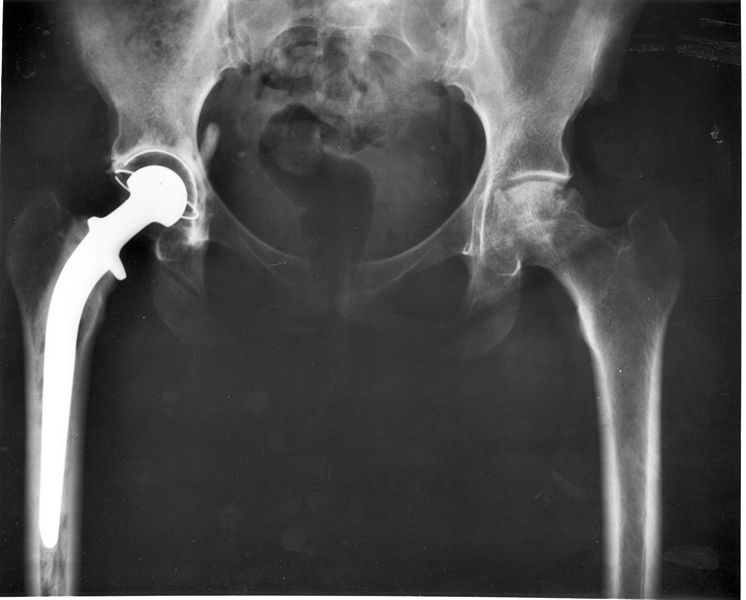

This replaces the whole joint, both the femoral component and the hip socket, the acetabulum.

Due to losing all the structures around the hip joint, such as the ligamentous capsule and other ligaments, and the inherent instability of an artifical joint, this replacement is a last effort and is at a higher risk of dislocation.